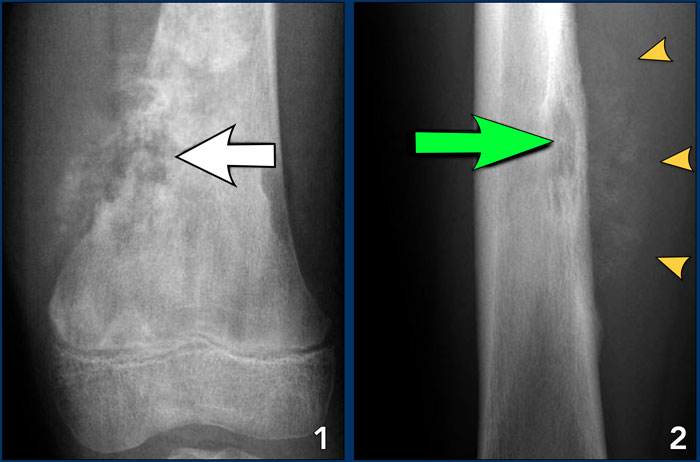

Aggressive periosteal reaction Aggressive periosteal reaction

Aggressive periosteal reaction (2)

1. Osteosarcoma with interrupted periosteal rection and Codman's triangle proximally (red arrow).

There is periosteal bone formation perpendicular to the cortical bone and extensive bony matrix formation by the tumor itself.

2. Ewing sarcoma with lamellated and focally interrupted periosteal reaction. (white arrows)

3. Infection with a multilayered periosteal reaction.

Notice that the periostitis is aggressive, but not as aggressive as in the other two cases.

Images

1. Osteosarcoma

Irregular cortical destruction

2. Ewing's sarcoma

Cortical destruction (green arrow) and aggressive periosteal reaction (arrow heads).